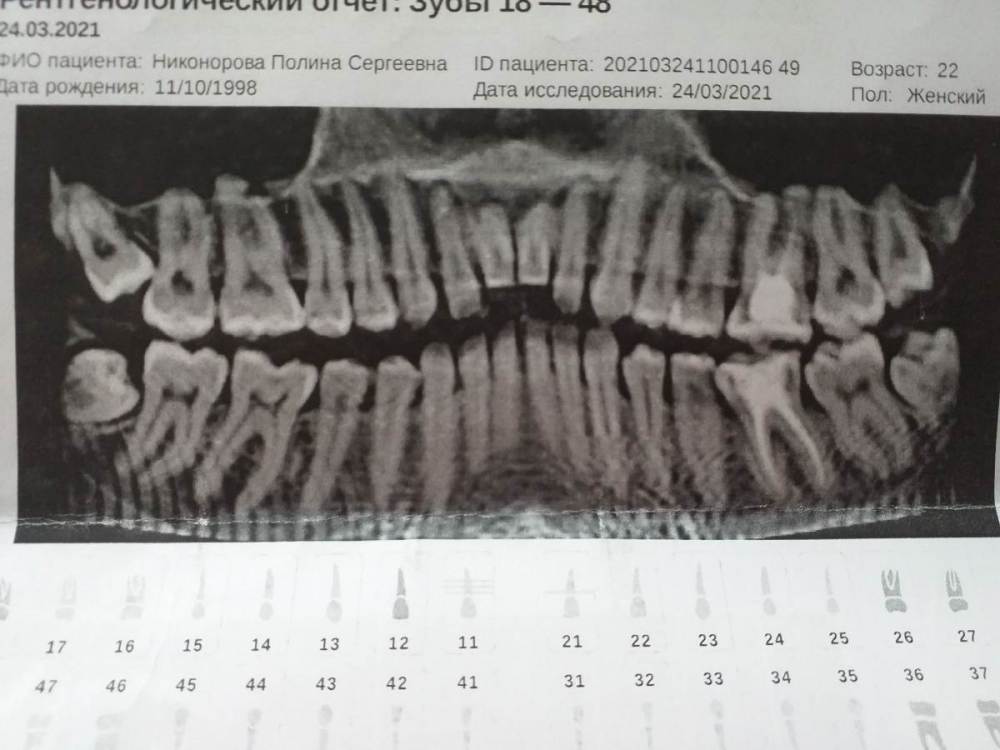

Скажите пожалуйста могут ли быть такие прострелы при дисфункции? Может ли быть такое чувство что присутствует проблема с глотанием и дыханием? Может не до конца залеченый зуб дает какие-то проблемы? Действительно ли мне нужно ставить шину  не усугубит ли она мое состояние? Ведь как я понимаю она будет выдвигать на место челюсть, а я уже как бы привыкла к такому ее неправильному положению, не будет ли страдать сустав ещк больше? При удалении зубов мудрости не пострадает ли больше челюсть? Может лезут зубы мудрости и дают какие-то симптомы? Может ли мне в будущем понадобится операция? Какие последствия могут быть если не лечится именно не ставить шину и брекеты? Можно ли после шины не ставить брекеты? Что мне в итоге делать с этим 26 зубом? Его берутся лечить за большие деньги, не давая при этом никаких гарантий. Что можете сказать о моем МРТ? Все врачи твердят, что ничего страшного нет. А по анализам? Снимок 26 зуба так же прилагаю, что же мне с ним делать?

20210416_184844.jpg

20210416_184833.jpg

20210416_184820.jpg

20210416_184754.jpg